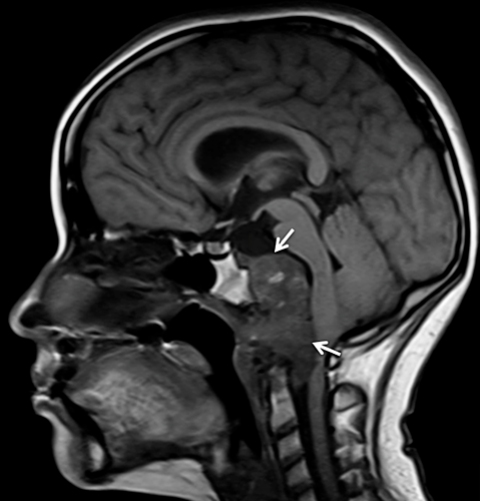

Magnetic resonance imaging (MRI): An MRI uses magnetic fields to produce detailed images of the body. A special dye called a contrast medium is injected into a patient’s vein before the scan to create a clearer picture.